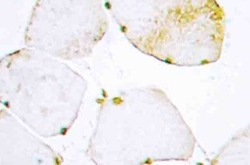

AP20519PU-N IHC

Full details

Method: